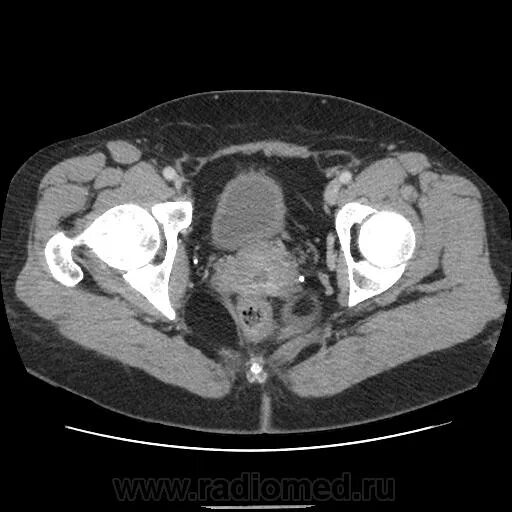

Где можно сделать кт малого таза